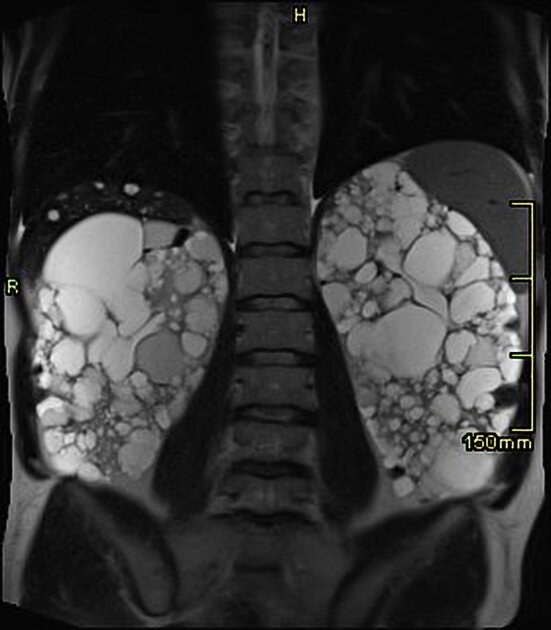

Um homem de 68 anos, com histórico médico de diabetes mellitus, hipertensão e acalasia, apresentou-se no

pronto-socorro com náuseas, episódios de vômito, falta de apetite e perda de peso (4,5 kg em 6 semanas).

Vale destacar que ele havia adotado uma dieta vegetariana cerca de 3 anos antes, como forma de melhorar o

controle do diabetes tipo 2. Nos últimos 6 meses, ele vinha consumindo diariamente cerca de 1 litro de suco de vegetais composto por espinafre cru, brócolis, couve-flor, feijão verde, aspargos, couve, beterraba, coentro, nabo,

cogumelos, cebola e inhame.

Exames laboratoriais revelaram níveis de creatinina de 9,6 mg/dl e ureia de 196 mg/dl, enquanto em exames

realizados meses anteriores, os valores de creatinina e ureia eram 1,4 mg/dl e 51 mg/dl, respectivamente. O exame do sedimento urinário mostrou a presença de 10 hemácias por campo, porém nenhum cristal foi observado.

Após tentativa de hidratação intensiva, não houve melhora clínica, sendo necessário iniciar a hemodiálise.

No décimo dia, foi realizada uma biópsia renal, que evidenciou uma grave lesão tubular com deposição intratubular difusa de cristais de oxalato (Figura 1A). A análise da biópsia revelou birrefringência característica quando observada sob luz polarizada (Figura 1B). Cristais de oxalato intratubular também foram identificados por microscopia eletrônica (Figura 1C). O paciente negou a ingestão de etilenoglicol ou vitamina C.